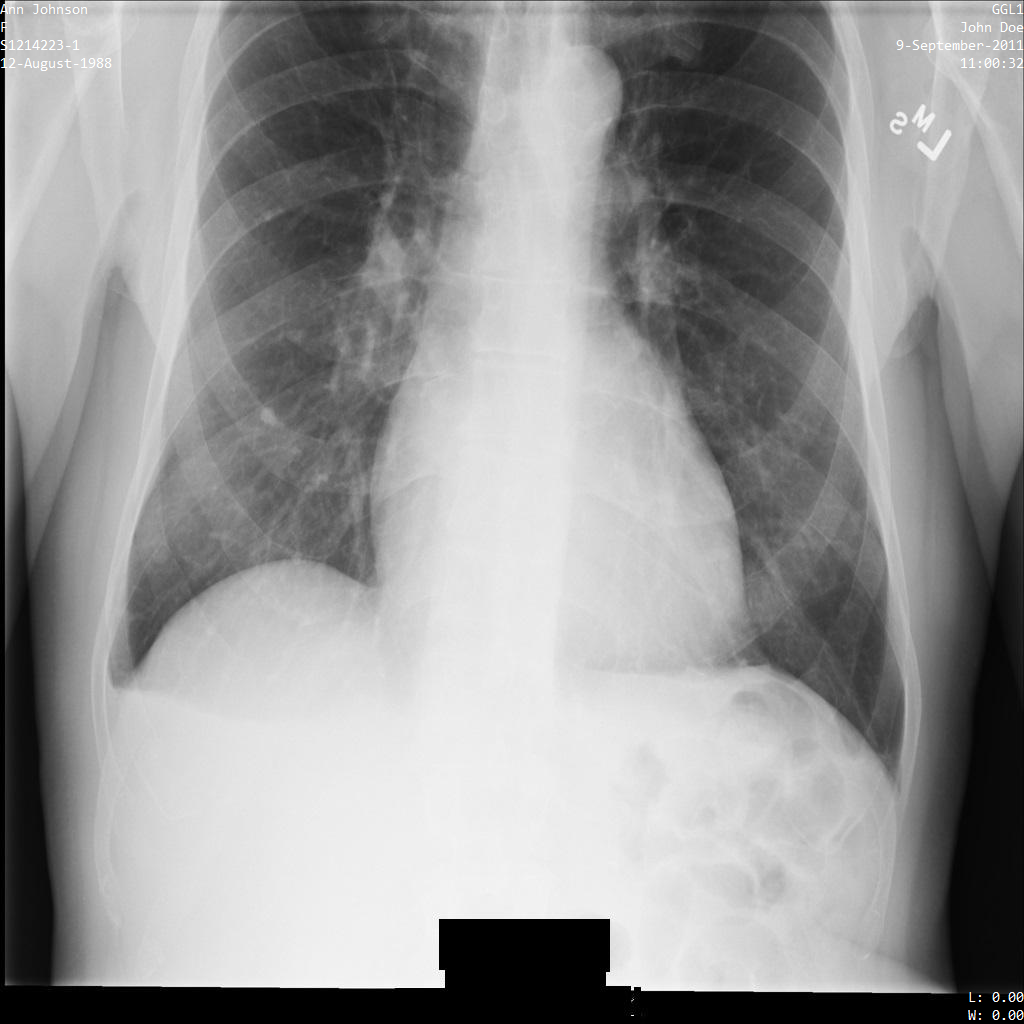

使用 ATTRIBUTE_CONFIDENTIALITY_BASIC_PROFILE 标记过滤条件配置文件将图片提交到 Cloud Healthcare API 后,图片显示如下。虽然图片顶部角落显示的元数据已被遮盖,但图片底部的烧屏 PHI 仍会保留。如需一并移除烧屏文字,请参阅遮盖图片中的烧屏文字

dicom_attribute_confidentiality_basic_profile